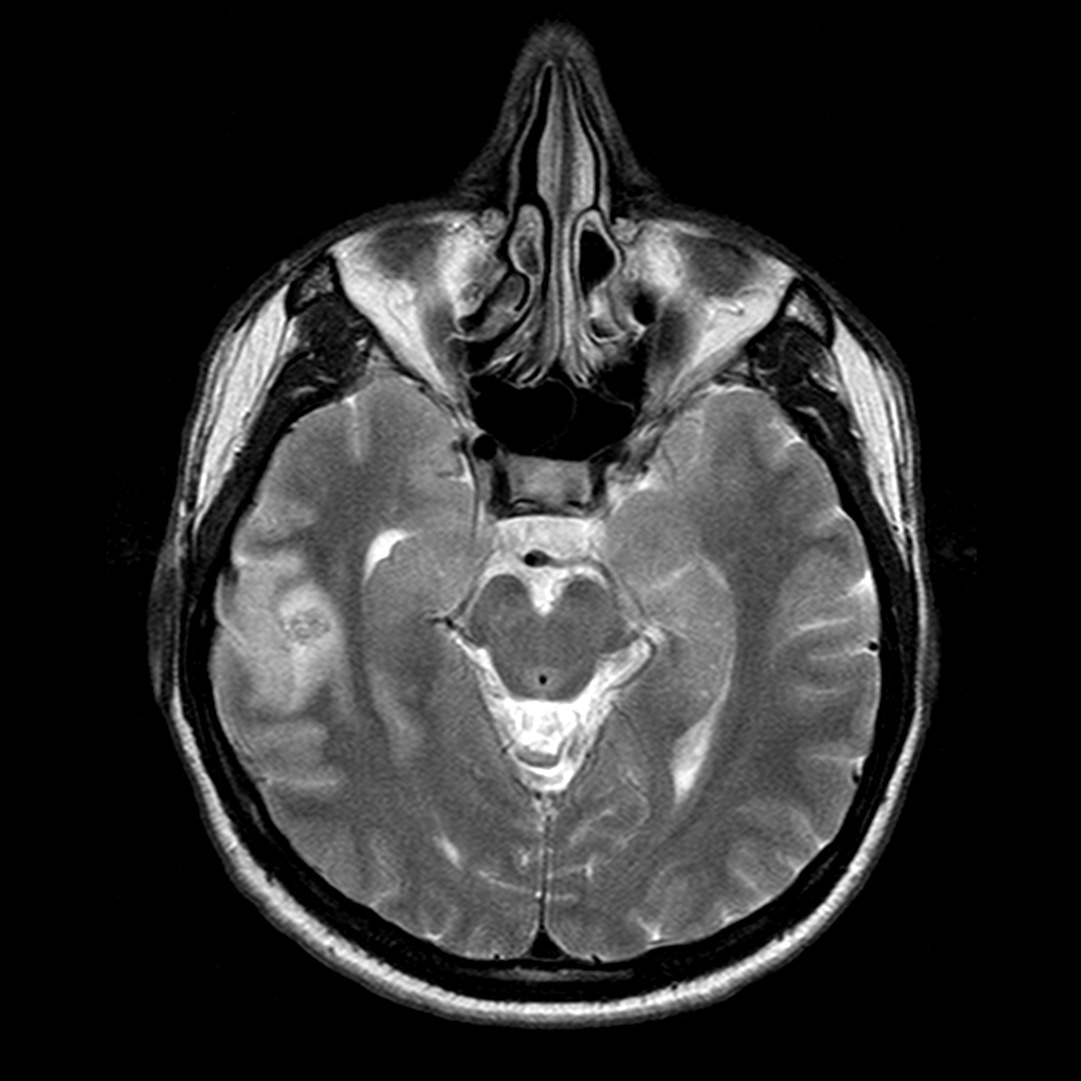

Se decide realizar una RM y una venografía RM para descartar una TVC. Ante el mal estado de la paciente, la cual no colabora, solo se puede terminar realizando secuencias FLAIR y Difusión.

El protocolo de estudio debe incluir secuencias FLAIR, T1(con y sin contraste), T2, y T2*, así como secuencias de difusión (DRM) y venográficas.

Secuencias convencionales de RM:

- Signos directos: Señal hiperintensa del seno trombosado en T1, que indica la ausencia de flujo y la presencia de material trombosado. Un falso positivo sería la señal hiperintensa por éstasis sanguíneo; para solucionarlo usar estudio contrastado y ver el delta vacío u obtener secuencias en diferentes planos del espacio. Por otra parte, el trombo, al igual que la sangre, presenta cambios en su evolución. En fase hiperaguda, será isodenso con respecto al LCR y por tanto es difícil valorarlo. Para solucionarlo, podemos usar secuencias T1 con contraste y ver el «stop» del flujo o usar secuencias T2 gradiente, ya que es muy sensible a la desoxihemoglobina que contiene el trombos fresco.

- Estadio 3: Moderado edema y mayor aumento de PIC. Leve aumento de señal parenquimatosa en T2 ponderado y FLAIR.